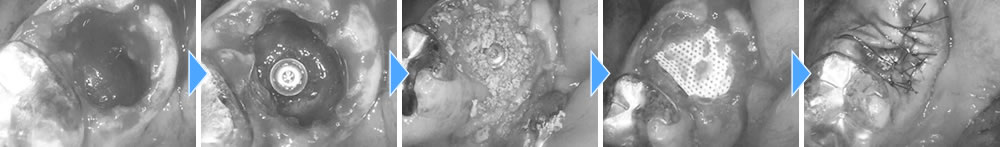

抜歯即時埋入インプラントの実施

まずは、歯根が破折している当該歯を抜歯しました。

抜歯直後にインプラントを埋入しました。骨欠損の範囲が大きかったため、骨造成も同時に行いました。

上部構造の装着・治療完了

治癒期間を経て、インプラントと顎骨が結合していることを確認した後、製作した上部構造(ジルコニアクラウン)を装着して治療完了となりました。